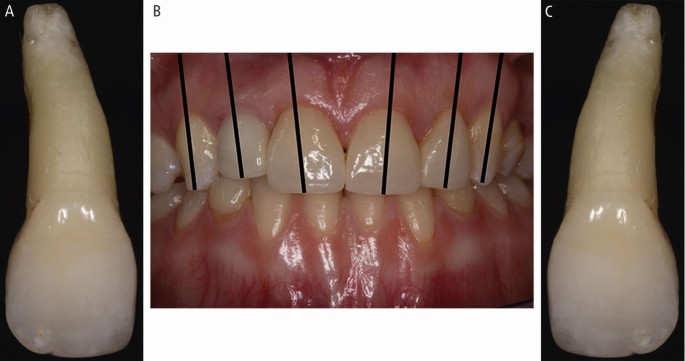

Identifying multiple, avulsed teeth (Fig. 22)

Fig. 22 (A, B, C) To identify multiple avulsed teeth: maxillary centrals are largest, canines are ‘pointed', and root inclination distinguishes left from right